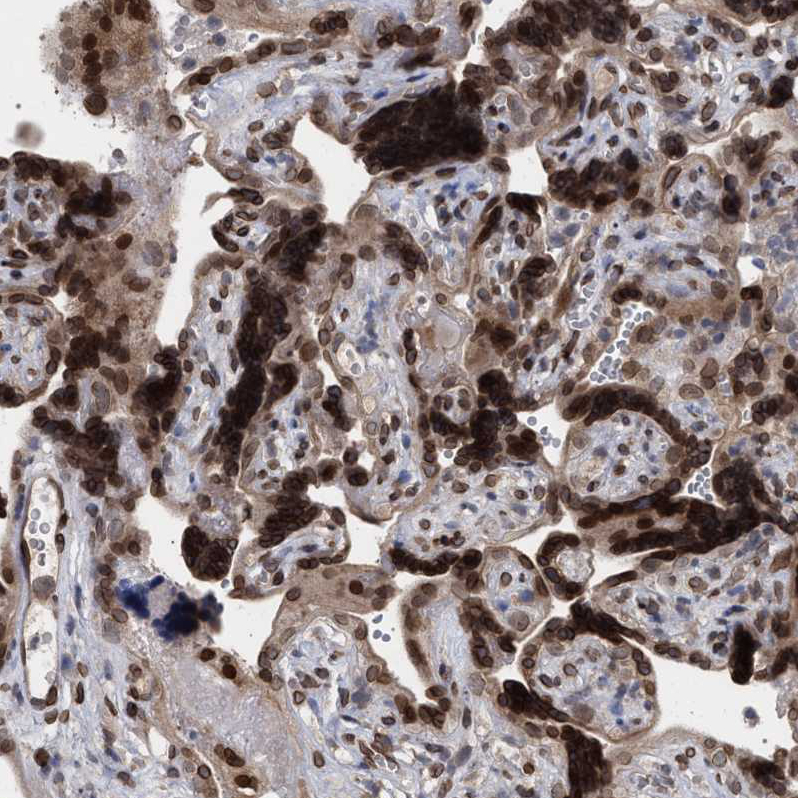

Immunohistochemical staining of human colon shows strong nuclear membrane positivity in glandular cells.